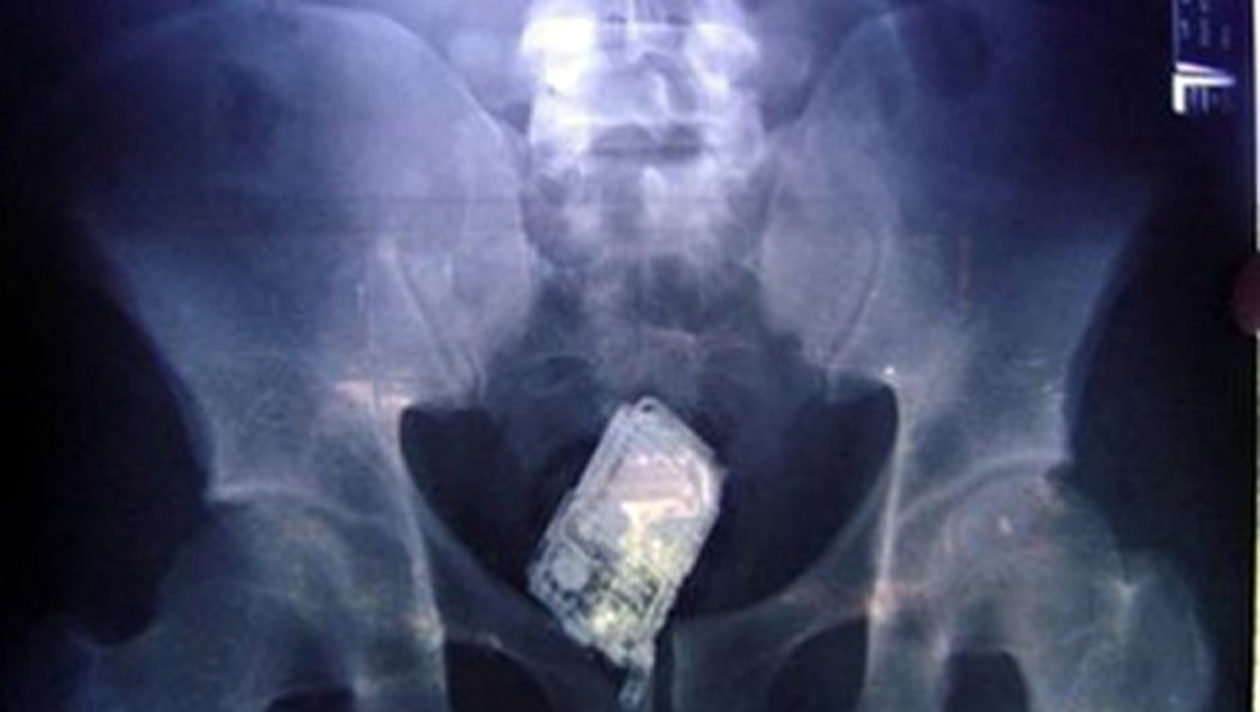

Un detinut incarcerat pentru furt la Penitenciarul Slobozia si adus la Penitenciarul de la Poarta Alba pentru un proces, a fost dus la spital dupa ce si-a introdus in anus un telefon mobil.

„In urma cu doua seri (miercuri seara – n.r.), in timpul unui control de rutina, detectorul de metale a identificat o anomalie in zona abdomenului detinutului respectiv. El a fost dus la cabinetul medical al penitenciarului, unde a recunoscut ca si-a introdus un telefon mobil in anus”, a declarat purtatorul de cuvant al Penitenciarului Poarta Alba, care a precizat ca detinutul a refuzat sa spuna de unde a avut telefonul mobil.

Barbatul a fost transportat la Spitalul Clinic Judutean de Urgenta Constanta unde i s-a facut o radiografie, care a confirmat existenta telefonului mobil, dar detinutul a refuzat orice interventie pentru scoaterea aparatului. El a fost dus, joi, inapoi la Slobozia, iar gardienii vor astepta ca acesta sa elimine aparatul pe cale naturala.

Daca acest lucru nu va fi posibil, atunci el va fi supus unei interventii chirurgicale.